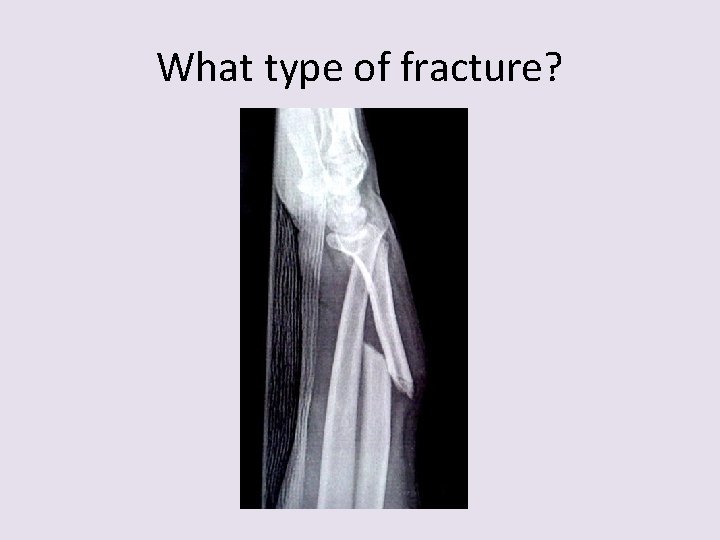

What type of fracture?